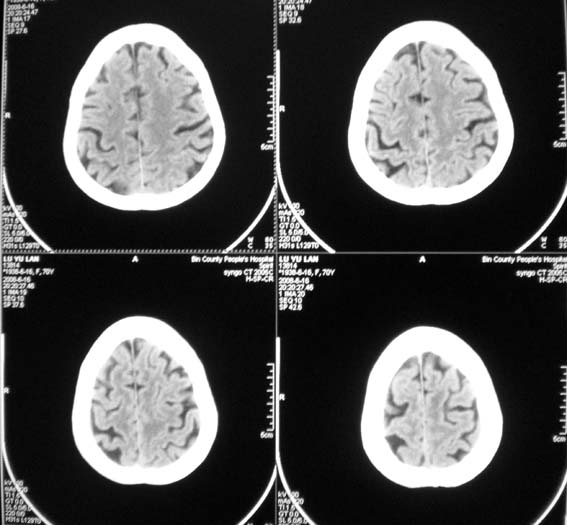

女,70岁,双肺结核,头痛,肿胀包块半年余,逐渐增大。

溶骨性破坏,未见明确死骨;病灶边缘不整,我考虑为颅骨转移瘤可能性大。建议仔细询问病史,积极寻找原发病灶。肺部如果扫描,最好请一并上传。

ct14067:颅骨破坏结果,转移瘤!

肝脏ct示肝癌,颅骨为转移所致!